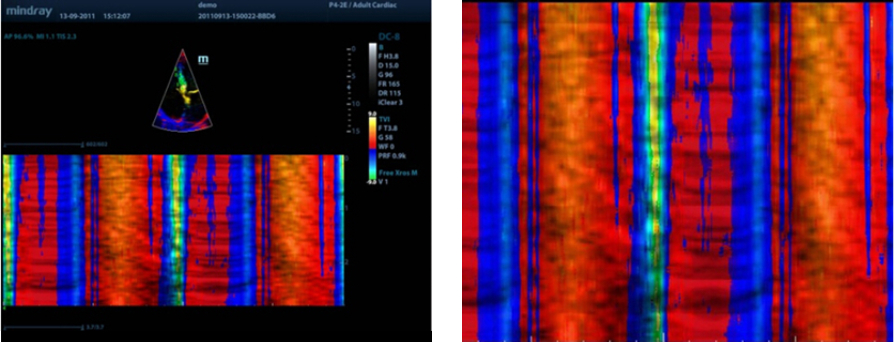

Free Xros CM?

Voor nauwkeurige evaluatie van myocardbeweging in verschillende fasen, en tegelijk bepaling van myocardiale synchronisatie. Hoge framesnelheid biedt nauwkeurige resultaten:

TDI

Met Tissue Doppler Imaging kunt u de plaatselijke myocardbeweging en -functie kwantitatief evalueren met volledige TDI-modi voor snellere en directe diagnoses.